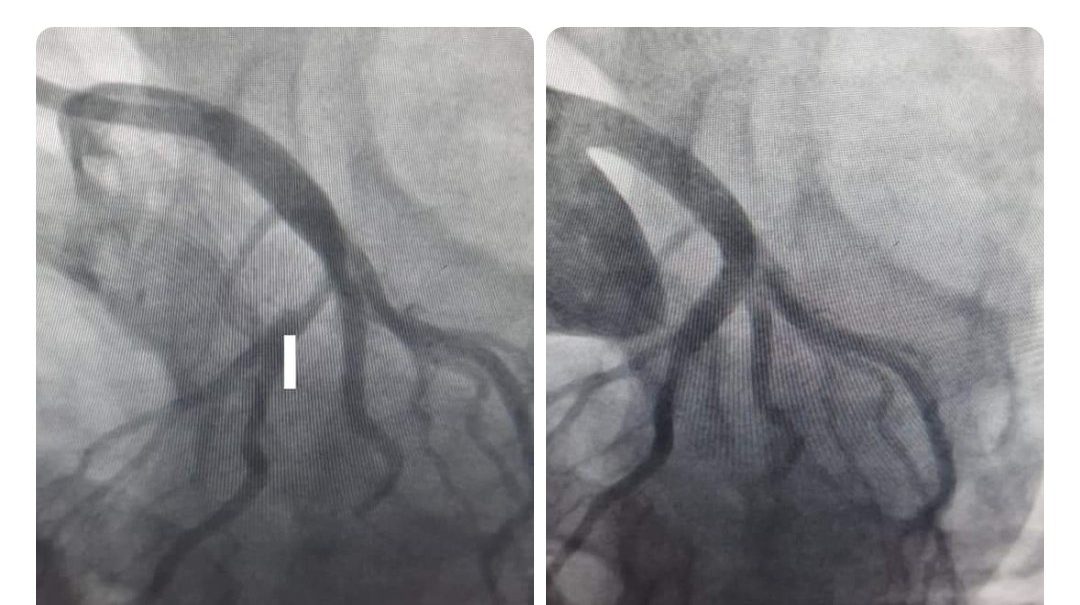

आज कै कुरा गरौँ हृदयघात भई शहीद गंगालाल राष्ट्रिय हृदय केन्द्रमा उपचारका लागि आएका एक जना २९ बर्षका बिरामी धूमपान प्रयोगकर्ता थिए ।

कोरोना कहरका बीचमा पनि ‘प्राइमरी एनजिओप्लास्टी गरी उनको बन्द भएको मुटुको धमनी खोलियो ।

हृदयघात भएको लक्षण (छाती दुख्नु) शुरु भएको १२ घण्टा भित्र गरिने यो उपचार उत्कृष्ठ उपचार हो ।